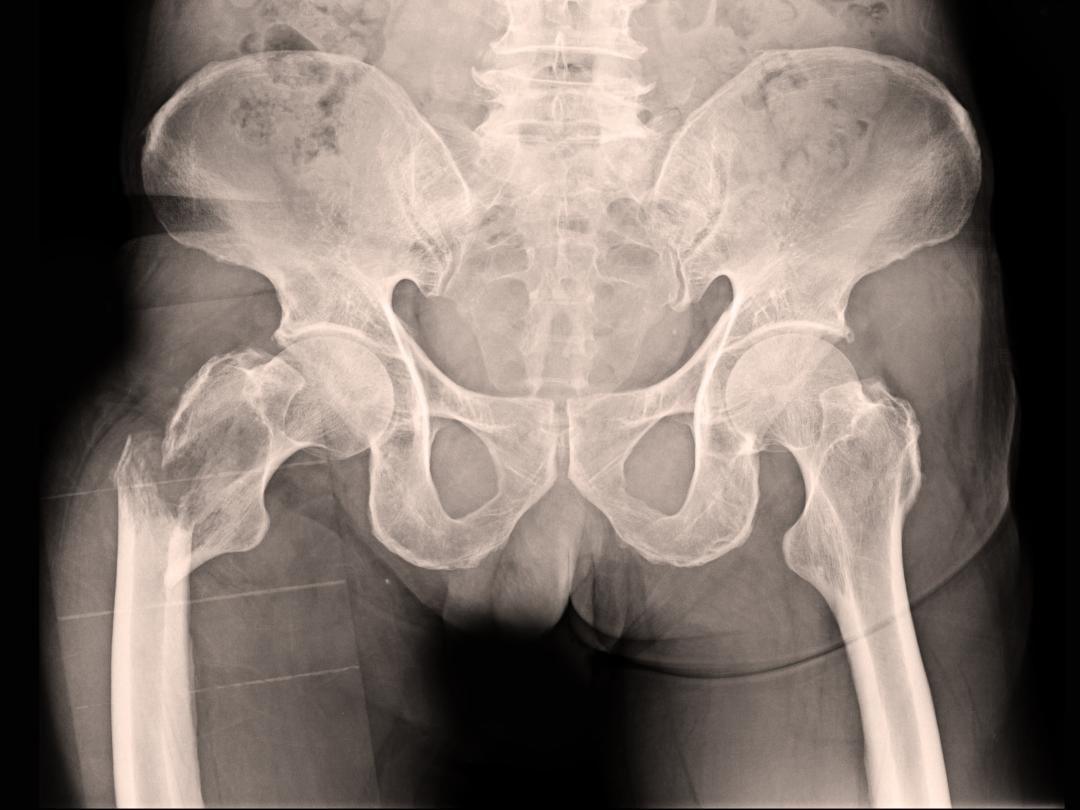

Röntgen van het bekkengebied

Een 81-jarige vrouw bekend met dementie, atriumfibrilleren en diastolisch hartfalen, kwam op de SEH terecht vanwege een heupfractuur. Na overleg met de echtgenoot werd besloten een osteosynthese te verrichten. Na de operatie kreeg zij een wegraking en werd ze opgenomen op de IC, hoewel ze had gezegd dat niet te willen. Zij kreeg een symptoomgerichte behandeling en overleed een dag na de operatie.